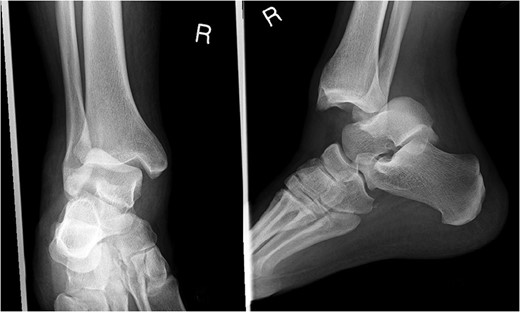

A 30-year-old male patient presented to Emergency Department (ED) following a run over injury. The patient described the mechanism of injury as moving his body over his run over foot. On clinical examination, there was obvious deformity and swelling of the right ankle. Dorsalis pedis pulse was felt but weak compared to the contralateral side with a capillary refill time under 3 s. The posterior tibial artery could not be palpated because of the deformity. X-rays showed posterior ankle dislocation without associated fractures (Fig. 1). Urgent reduction of the dislocation was done under sedation in ED. The knee was first flexed to relax the tendon Achilles then longitudinal traction with gentle forward force applied to the heel with immediate reduction of the deformity achieved. The foot was reassessed for vascular status. Triphasic pulse in both drosalis pedis and posterior tibial artery was detected with hand held Doppler. Ankle was immobilized in posterior below knee back slab to accommodate for swelling and check x-rays confirmed reduction of the ankle joint (Fig. 2). CT scan was done afterwards to define any subtle incongruity or osteochondral fragments entrapped in the joint. CT did not show any associated fractures and showed congruent reduction of the ankle joint (Fig. 3). Patient was mobilized touch weight bearing for first 2 weeks. The back slab was changed for weight bearing short leg cast and progressive weight bearing was allowed for the following 4 weeks. At 6 weeks follow up, plaster was removed and on examination patient still had moderate tenderness over the medial joint line and deltoid ligament area. Also, patient had limited range of plantar and dorsal flexion. Referral for physiotherapy was done for start of functional rehabilitation and range of motion exercises and in mean time MRI was done to delineate extent of ligamentous injury. MRI showed bone bruising of the lateral malleolus, medial malleolus and lateral talus (Fig. 4). The anterior talufibular ligament (ATFL), calcaneofibular ligament (CFL), posterior talofibular ligament (PTFL) and deltoid ligaments were sprained but intact. At 12 weeks follow up, patient could walk normally without any symptoms of instability and achieved 20° of both plantar and dorsal flexion. At 16 weeks, patient achieved full range of motion of ankle and was able to return to work. At 24 weeks follow up patient was able to resume his sport activates as preinjury level.

Post reduction films showing adequate reduction of the ankle joint with no talar shift or syndesmotic injury.